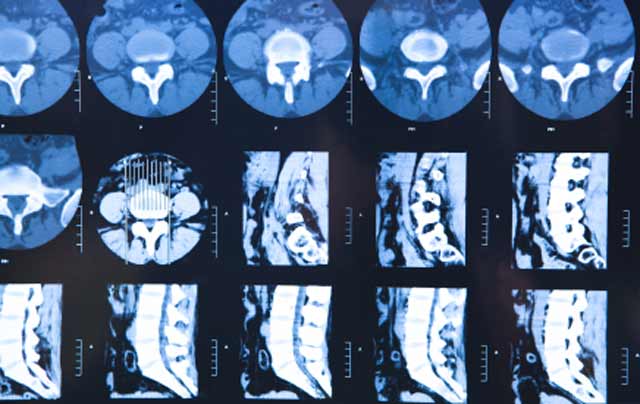

Oxford Spinal Surgery Unit is dedicated to the diagnosis, investigation and treatment of all types of spinal problems deriving from sports injuries, accidents, hereditary and developmental conditions, and all aspects of arthritis.